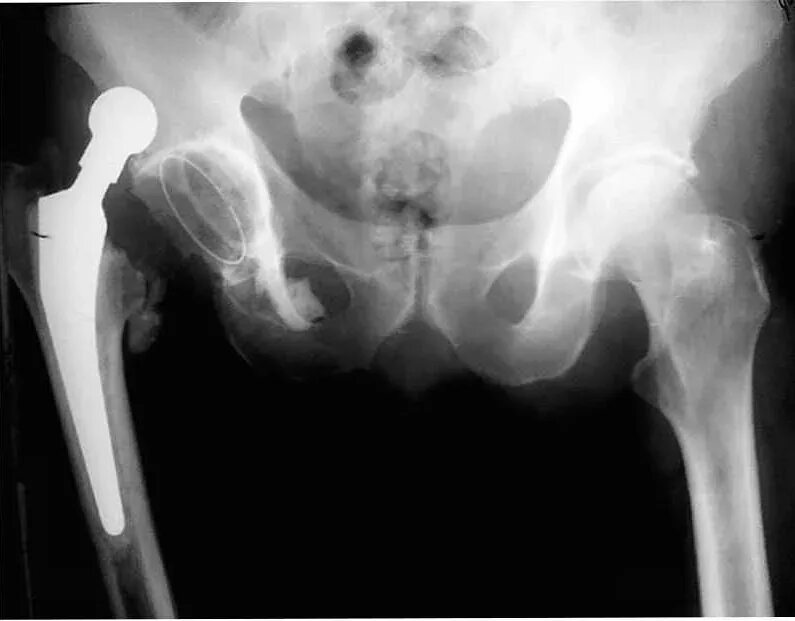

Вывих тазобедренного сустава симптомы